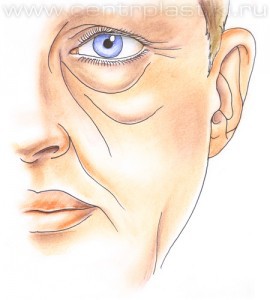

Рис. 4 Подтяжка средней зоны лица может быть выполнена всем пациентам, но наиболее часто выполняется при наличии выраженных возрастных изменений в области век и в средней зоне лица, таких как выраженные выпячивания жира под глазами, слезные, веко-щечные, скуловые борозды, «малярные» или скуловые «мешки». Рис. 5. Она также показана пациентам после ранее перенесенной традиционной блефаропластики на нижних веках, пациентам имеющие «западение» нижних век после чрезмерного удаления жировой клетчатки в области нижних век, как коррегирующая (улучшающая) операция при округлении глаз, при незначительном вывороте нижнего века.

Рис. 6 Мышцу, аккуратно приподнимают и отделяют до края глазницы. Рис.7. Жировые «грыжи» опускаются вниз за край глазницы и фиксируются к надкостнице несколькими нитями, Рис. 8-9 таким образом, удается заполнить слезную и веко-щечную борозды Рис. 10.

Рис. 9 Через боковую часть разреза выполняется отделение надкостницы от костей в проекции средней зоны лица вниз до крыла носа, обычно для этого используются эндоскопические инструменты. Рис. 11 Мобилизованные ткани прошиваются в верхненаружном углу и фиксируются к надкостнице выше наружного угла глаза. Рис. 12 Выполняется миопексия (фиксация мышцы окружающей глаз) Рис. 13 и кантопексия (фиксация наружного угла глаза), Рис. 14 затем удаляется избыток кожи Рис. 15. Этим достигается правильное положение глазной щели и удается добиться разглаживания мелких морщин. В конце операции кожная рана зашивается косметичным внутрикожным швом.